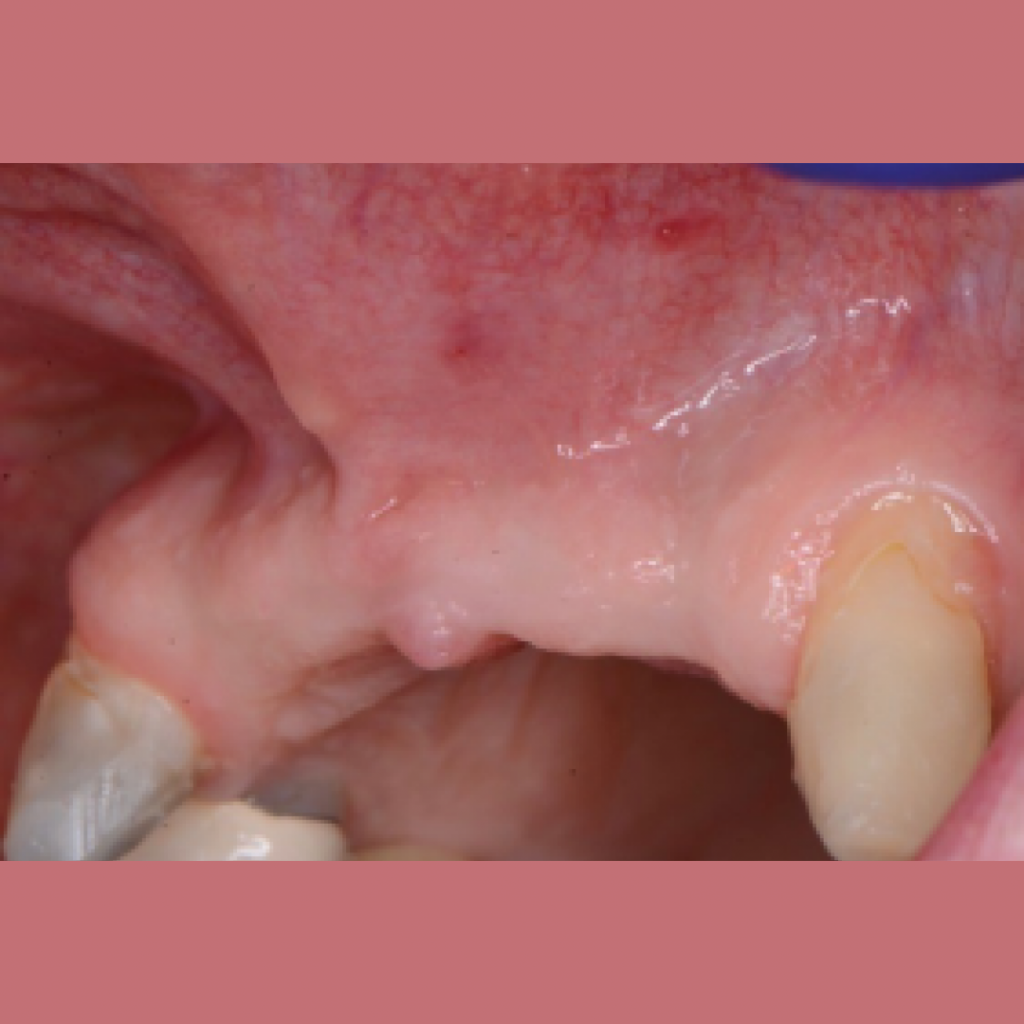

Имплантация AnyOne в узкий гребень. Восстановление зубов 11,12,21,22 на двух имплантатах.